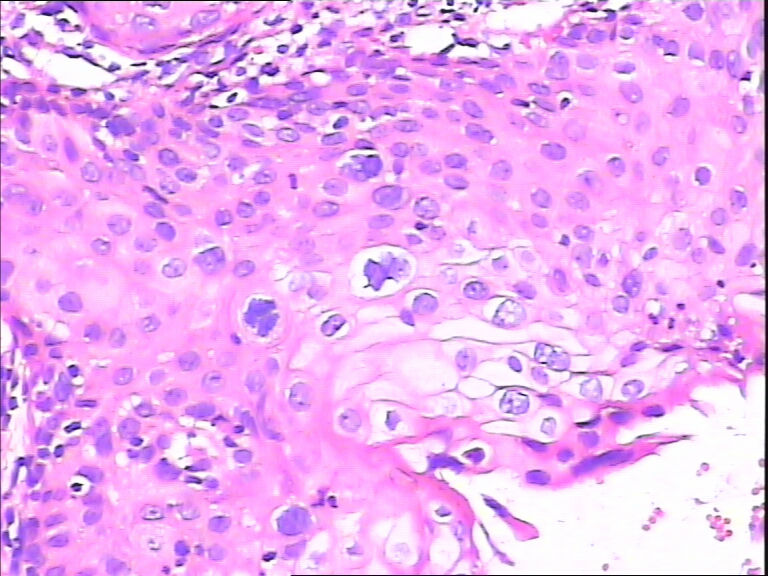

45y,触血,宫颈多点活检。